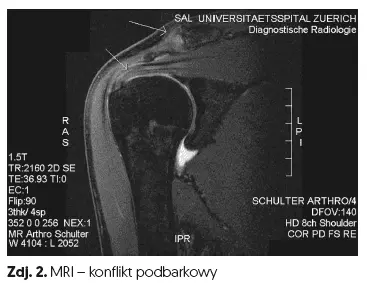

Obszar pomiędzy głową kości ramiennej a wyrostkiem barkowym jest nazywany przestrzenią podbarkową. W tej przestrzeni znajdują się: ścięgno mięśnia nadgrzebieniowego (jeden z mięśni stożka rotatorów), długa głowa ścięgna mięśnia dwugłowego ramienia, kaletka podbarkowa i torebka stawu barkowego.